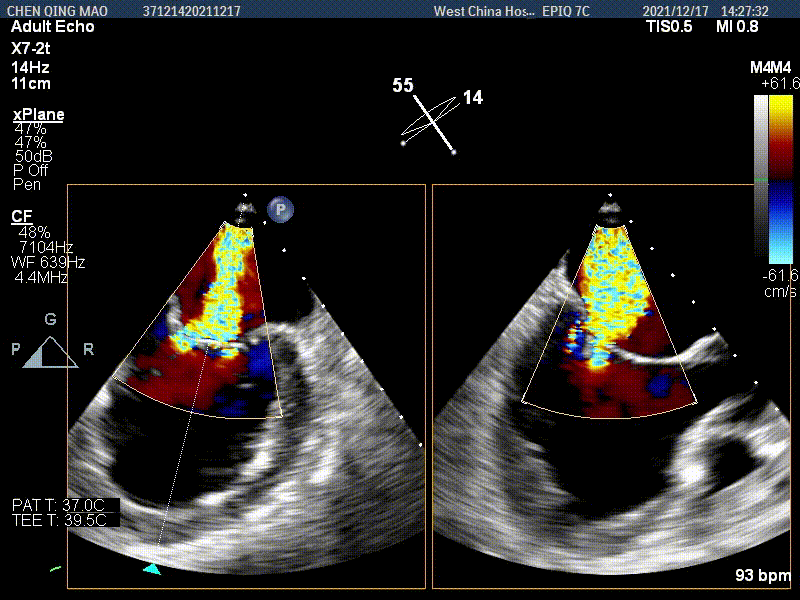

术后即刻超声评估

这是我们团队应用Peijia HighLife TSMVR系统完成的第二例经房间隔二尖瓣置换术,切实感受到该系统的易操作性、巧思设计和标准化术式步骤对于手术结果与患者获益的保障。本例的Looping时长较第一例缩短了一半时间。“Valve-in-Ring” 非径向支撑力锚定、瓣膜释放时自同轴自适应,使得人工瓣膜与二尖瓣环有良好的贴靠, 术毕二尖瓣返流消失。相信经外周血管入路的二尖瓣置换前景可期,可以为更多二尖瓣返流患者带来治疗的获益。